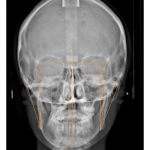

• A través de sencillas pero poderosas herramientas se pueden hacer trazados cefalométricos que permitan al médico observar, analizar y/o diagnosticar detalladamente y con mayor rapidez y confiabilidad.

- Frontal